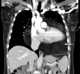

Pericardial lipoma